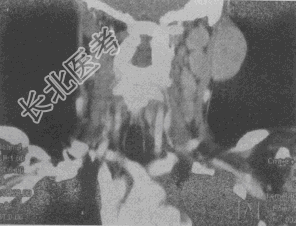

- 单项选择题女,25岁, 发现双侧颈部肿块近10年,CT如图, 最可能的诊断为

A、巨淋巴结增生症

B、淋巴瘤

C、转移瘤

D、淋巴结结核

E、淋巴结炎